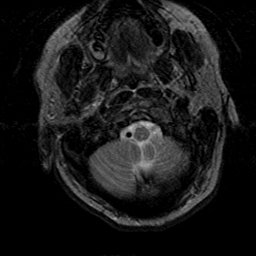

Subacute Stroke, overlay -- Slice #1

[Home][Help][Clinical] Slice 1